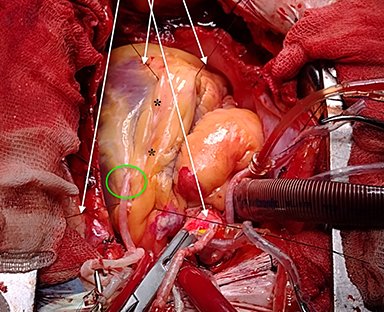

En esta sección se visualizarán cirugías reales en pacientes. Las fotografías por lo tanto

-si bien claras- en ocasiones privilegian la seguridad del paciente antes de

la exposición anatómica ideal.